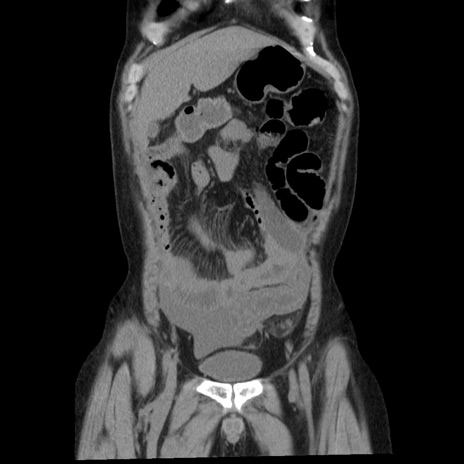

症例29(冠状断像)

症例

【症例】40歳代男性

【現病歴】2日前から胃痛あり。徐々に周期的な激痛に変化した。本日になっても激痛があるため受診。

【既往歴】なし

【身体所見】意識清明、BT 38-39℃台あり、腹部:膨満、やや硬、右下腹部に圧痛あり。

【データ】WBC 8500、CRP 23.26